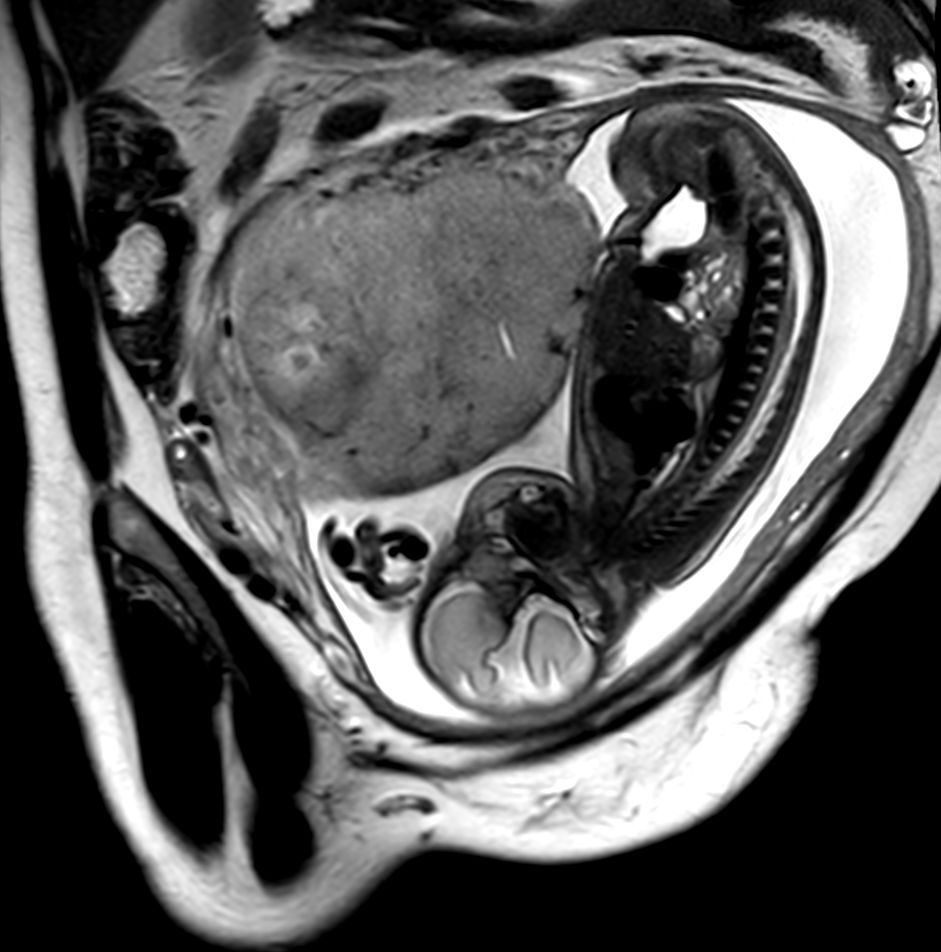

Pregnant patient, referred to MRI for fetal brain imaging because of suspected arachnoid cyst.

Sagittal T2w TSE single shot